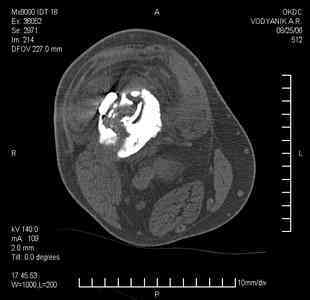

Уважаемые коллеги,В ортопедическое отделение обратился пациент: мужчина 47 лет, который в течение 4-х лет дваждыполучил травму костей, образующих правый коленный сустав. В 2002 v внутрисуставной оскольчатыйперелом проксимального метаэпифиза правой большеберцовой кости; в 2005 v внутрисуставнойоскольчатый перелом дистального метаэпифиза правой бедренной кости. В обоих случаях в разных лечебных учреждениях проводилось оперативное лечение переломов.При осмотре в отделении на основании результатов клинического осмотра и данных визуальныхметодов обследования поставлен диагноз:тугой ложный сустав дистальной трети правой бедренной кости, состояние после накостногоостеосинтеза перелома типа 33-В2.2 ; несросшийся перелом надколенника; неправильно сросшийсяперелом латерального мыщелка правой большеберцовой кости, состояние после металлоостеосинтезаперелома 41-В2.2; сочетанная осевая деформация правой ноги: варусная деформация правого бедра,вальгусная деформация правой голени; посттравматический артроз коленного сустава 4 ст по Kellgren-Lowrence; выраженное нарушение функции ходьбы и опоры. Внешний вид ноги больного, данные рентгенографического обследования и избирательно выделенные компьютерные томограммы приведены в приложении. В именах КТ использовано кодирование уровня по АО, т.е. _41, например, означает проксимальную треть голени.В отделении намечен v очень предварительно v следующий план лечения: 1. Иметь ввиду перспективу тотального эндопротезирования коленного сустава. 2. С учетом п.1 при проведении действий, направленных на устранение ложного сустава бедренной кости не использовать материалы, не подвергающиеся трансформации. 3. В ходе операции, направленной на устранение ложного сустава: А. удалить все металлоконструкции; Б. ревизовать зону пролежня под пластиной на бедре, при наличии признаков достаточной жизнеспособности кости выполнить остеопериостальную декортикацию, дрилинг ложа пластины; В. Удалить рубцовую ткань по плоскости ложного сустава, и в пространстве между костными форагментами, насечь обращенные друг к другу поверхности. Ввести штифт с блокированием (например Stryker с учетом особенностей расположения дистальных блокирующих винтов у этойконструкции). Осуществить остеосинтез с учтанением варусной деформации бедренной кости. Пространство в зоне ложного сустава и пустоты в метафизе бедренной кости заполнить резорбирующимся цементом на основе гидроксиапатита кальция. Для дистальной фиксации использовать винты с переменным шагом резьбы. Вариант:, винты вводить после заполнения метафиза цементом. Дополнительные виды создания межфрагментарной компрессии во встречно-боковом направлении обсуждаются. Г. Быть готовым к кровопотере. Д. Учесть высокий риск инфекции, тромбоэмболических осложнений. Е. Вопрос о внешней иммобилизации решить по результатам оценки стабильности остеосинтеза. Вариант - одноосевой стержневой аппарат для шунтирования гвоздя с модулем на голени и дистракцией коленного сустава в течение 3-5 недель. Просим вашей критики намеченного плана и конструктивных предложений. С уважением к сообществу, Ординатор В.С. Саплин

Движения приличные, есть за что бороться. Такая ротация голени кнаружи, если она действительно есть (для уточнения можно сделать КТ на уровне обоих метафизов и бедреных, и берцовых ксотей, не меняя положение ног во время съемки), большого значения не имеет. А уж на фоне всего остального тут - вообще говорить не о чем.